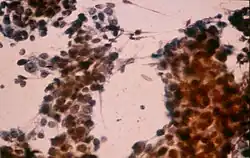

Wątrobiak zarodkowy, hepatoblastoma, wątrobiak płodowy – rzadki złośliwy guz wątroby wieku dziecięcego. Utworzony jest z komórek przypominających komórki płodowej lub niedojrzałej wątroby i wewnątrzwątrobowych dróg żółciowych. Objawem prowadzącym do rozpoznania jest zazwyczaj macalny przez powłoki brzuszne guz. Często podwyższony jest poziom alfa-fetoproteiny (AFP), rokowanie jest gorsze w przypadkach z niepodwyższonym poziomem AFP[2].